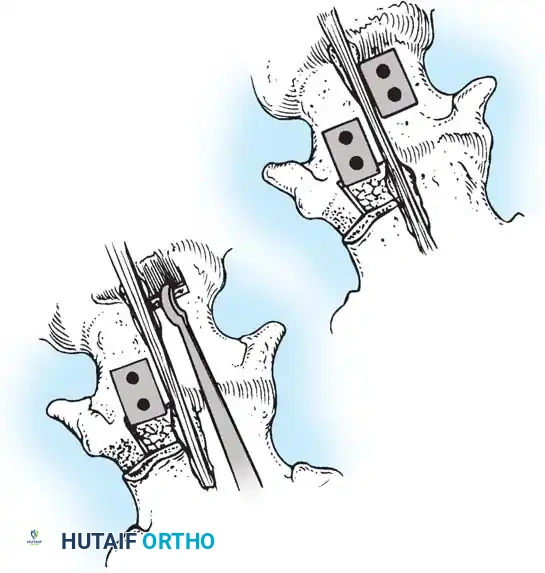

The Hall Technique

The Hall technique offers an alternative method for facet obliteration and grafting, particularly useful in rigid deformities.

Fig. 38-28: The Hall technique of facet fusion, involving sharp excision of the inferior facet and trough creation.

- Sharply amputate the inferior articular facet with a gouge and remove the bone fragment entirely. This exposes the cartilage of the superior facet.

- Remove the exposed cartilage completely with a sharp curet.

- Create a bleeding trough by removing the outer cortex of the superior facet.

- Impact cancellous bone grafts directly into this vascularized trough.

- Complete the procedure with global decortication of the posterior elements.